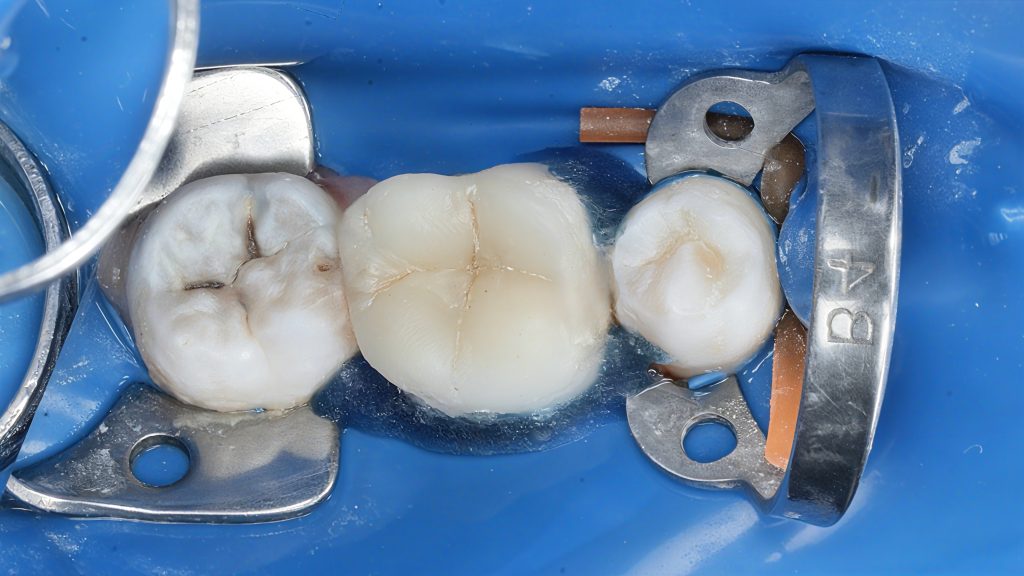

2. Isolation & Access

(Images 2–3)

Full rubber dam isolation for contamination control. Previous fillings removed, caries outlined, and access refined under magnification.